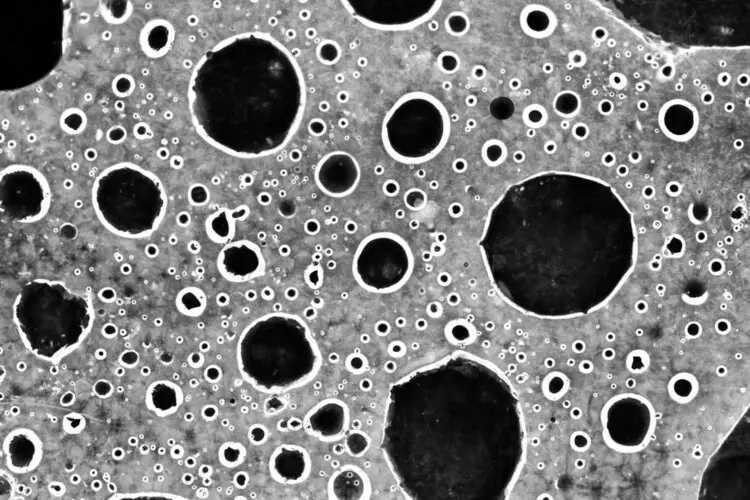

原位癌:人体表面及体内脏器表面都覆盖着一层组织,这层组织又被称为上皮组织。而长在上皮组织的恶性肿瘤就被称为原位癌。原位癌的癌细胞只能局限于上皮组织内,并未破坏粘膜或皮肤的基底膜侵犯到周围组织,更没有发生浸润和远处转移。

原位癌是最早期的癌症,严格来讲,只能称得上是癌前病变,故原位癌又称为0期癌。患者不会出现明显症状,也不会危及生命,有些还可自行消退。

浸润癌:当位于原位癌的癌细胞突破了上皮组织层,浸入基底膜后,就从原位癌变成了浸润癌。当然,这个过程一般要经过几年甚至几十年。早期的浸润癌一般不会出现转移,癌灶扩散很慢。